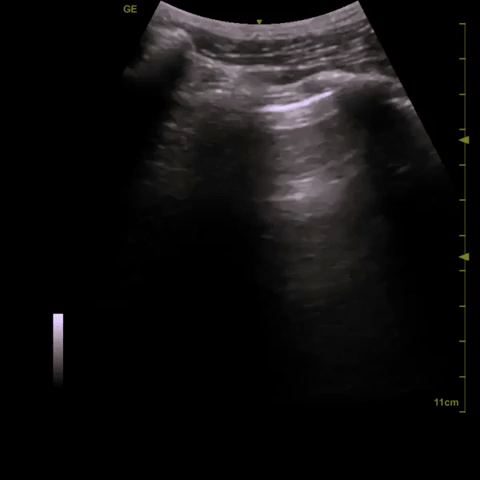

Here are clips from the initial lung POCUS: